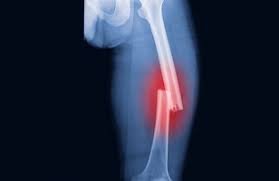

क्लीवलैंड क्लीनिक की रिपोर्ट के मुताबिक ऑस्टियोपोरोसिस की समस्या धीरे-धीरे विकसित होती है, कई लोगों को तो यह पता ही नहीं चलता है कि वह ऑस्टियोपोरोसिस के शिकार हो गए हैं। इतना ही नहीं समय के साथ हड्डियां इतनी कमजोर हो जाती हैं कि हल्के से ठोकर, यहां तक कि खांसने या छींकने से भी इनके टूटने का जोखिम हो सकता है। सभी लोगों को इसके जोखिम कारकों को समझते हुए बचाव के उपाय करते रहना चाहिए। आइए आगे इस बारे में विस्तार से समझते हैं।

स्वास्थ्य विशेषज्ञ कहते हैं, ऑस्टियोपोरोसिस के लक्षणों की पहचान करके समय रहते अगर उपचार शुरू कर दिया जाए तो इसकी जटिलताओं को कम किया जा सकता है। हालांकि शुरुआती चरणों में कई लोगों में इसके कोई भी लक्षण या संकेत नहीं दिखाई देते हैं, जिसके कारण इसका पहचान कर पाना कठिन हो सकता है। ज्यादातर मामलों में इस समस्या का पता तब तक नहीं चल पाता है जब तक कि उन्हें फ्रैक्चर न हो जाए। हालांकि कुछ लक्षणों को लेकर लोगों को सावधानी बरतते रहना चाहिए।